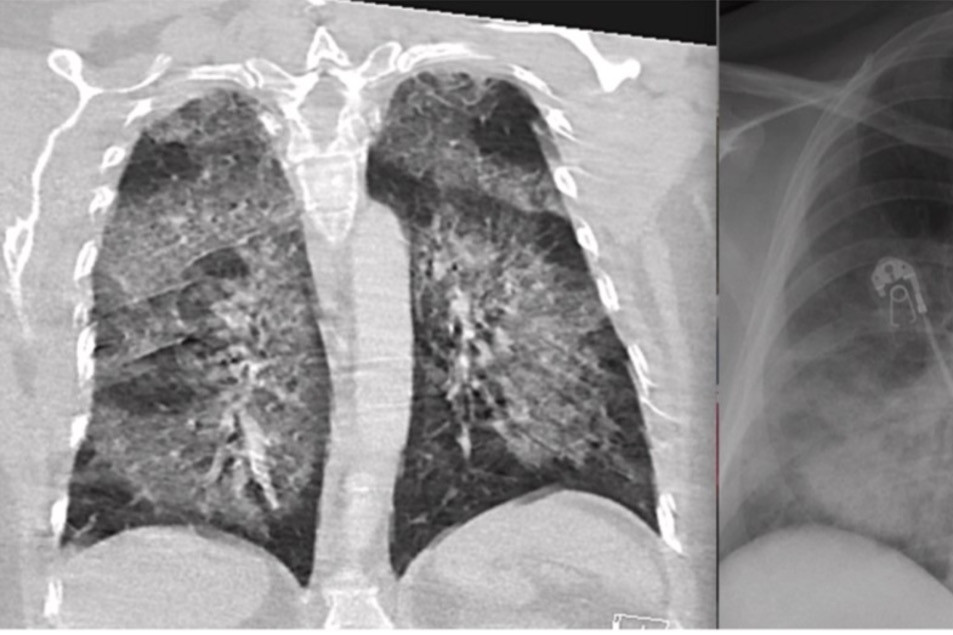

Hình ảnh phổi bị thuốc lá điện tử tàn phá nghiêm trọng

Theo các chuyên gia, việc sử dụng thuốc lá điện tử dẫn tới nhiều nguy cơ đối với sức khỏe, đặc biệt là làm tổn thương nghiêm trọng đến phổi.